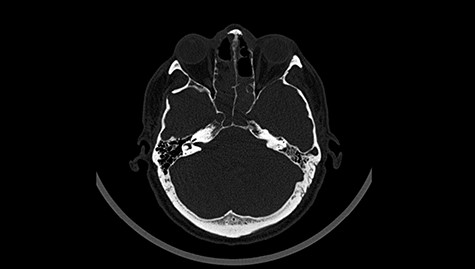

Head CT after polypectomy—seen defects of the upper left orbital wall. (Department of Neurosurgery own material).

In described case, a head CT scan after polypectomy confirmed the subarachnoid hemorrhage (Fig. 1). In addition, the presence of air in the ventricular system was visible, and presence of defects of the upper left orbital wall and ethmoid on both sides (Fig. 3). In the CT scan sphenoid sinus, frontal and ethmoidal sinuses on both sides and right maxillary sinus airless, filled with blood and soft tissue. The changes also concerned the lateral part of the left maxillary sinus (Fig. 4).

The present bone defects were most probably caused by the development of osteomalytic foci as a consequence of the spread of the inflammatory process within the diploe of flat skeletal skull bones, in the course of chronic rhinosinusitis. Both underestimating the severity of complaints in the course of chronic rhinosinusitis and delaying the implementation of surgical treatment led to massive bone destruction, which had an impact on the development of further complications after polypectomy (including subarachnoid hemorrhage). Performed angio-CT excluded any malformations and the probable cause of subarachnoid hemorrhage due to rupture of the aneurysm. Considering the radiological picture and the condition of the patient, it can be concluded that the persistent inflammatory process within sinuses led to dehsomination and subsequent bleeding into the subarachnoid space through discontinuity in the bone structure of the sinuses and orbits.